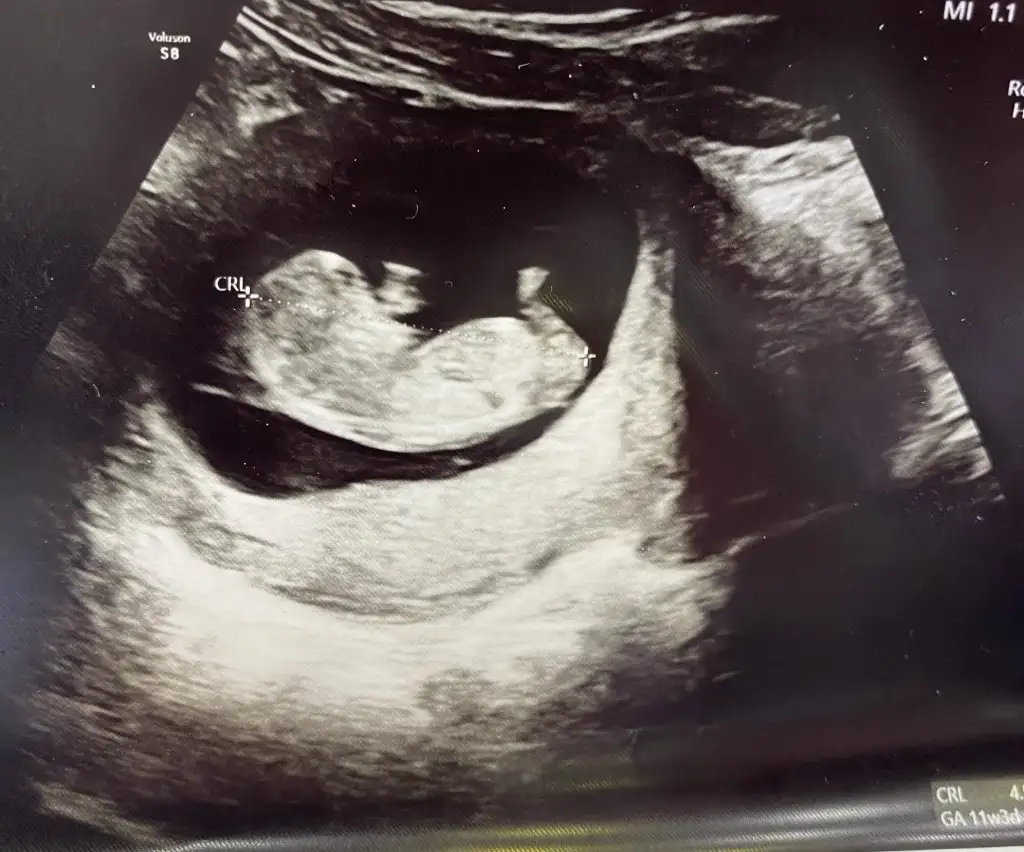

11 Haftalık olduk bizde kızlar tahminlerde değişen var mı bakabilir misiniz 🙋🏻‍♀️

Eklentiler

• IMG_5273.webp

IMG_5273.webp

35,9 KB · Görüntüleme: 61